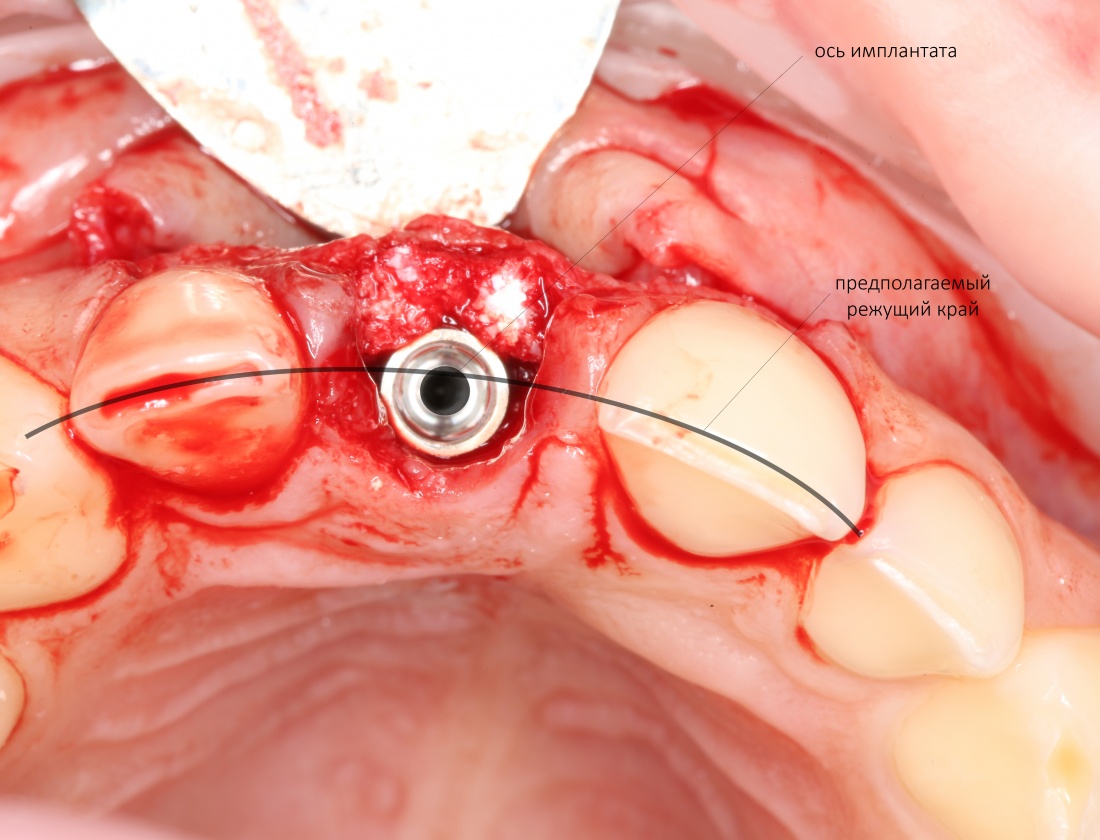

Рекомендации по установке имплантов. Для всех. Часть V.